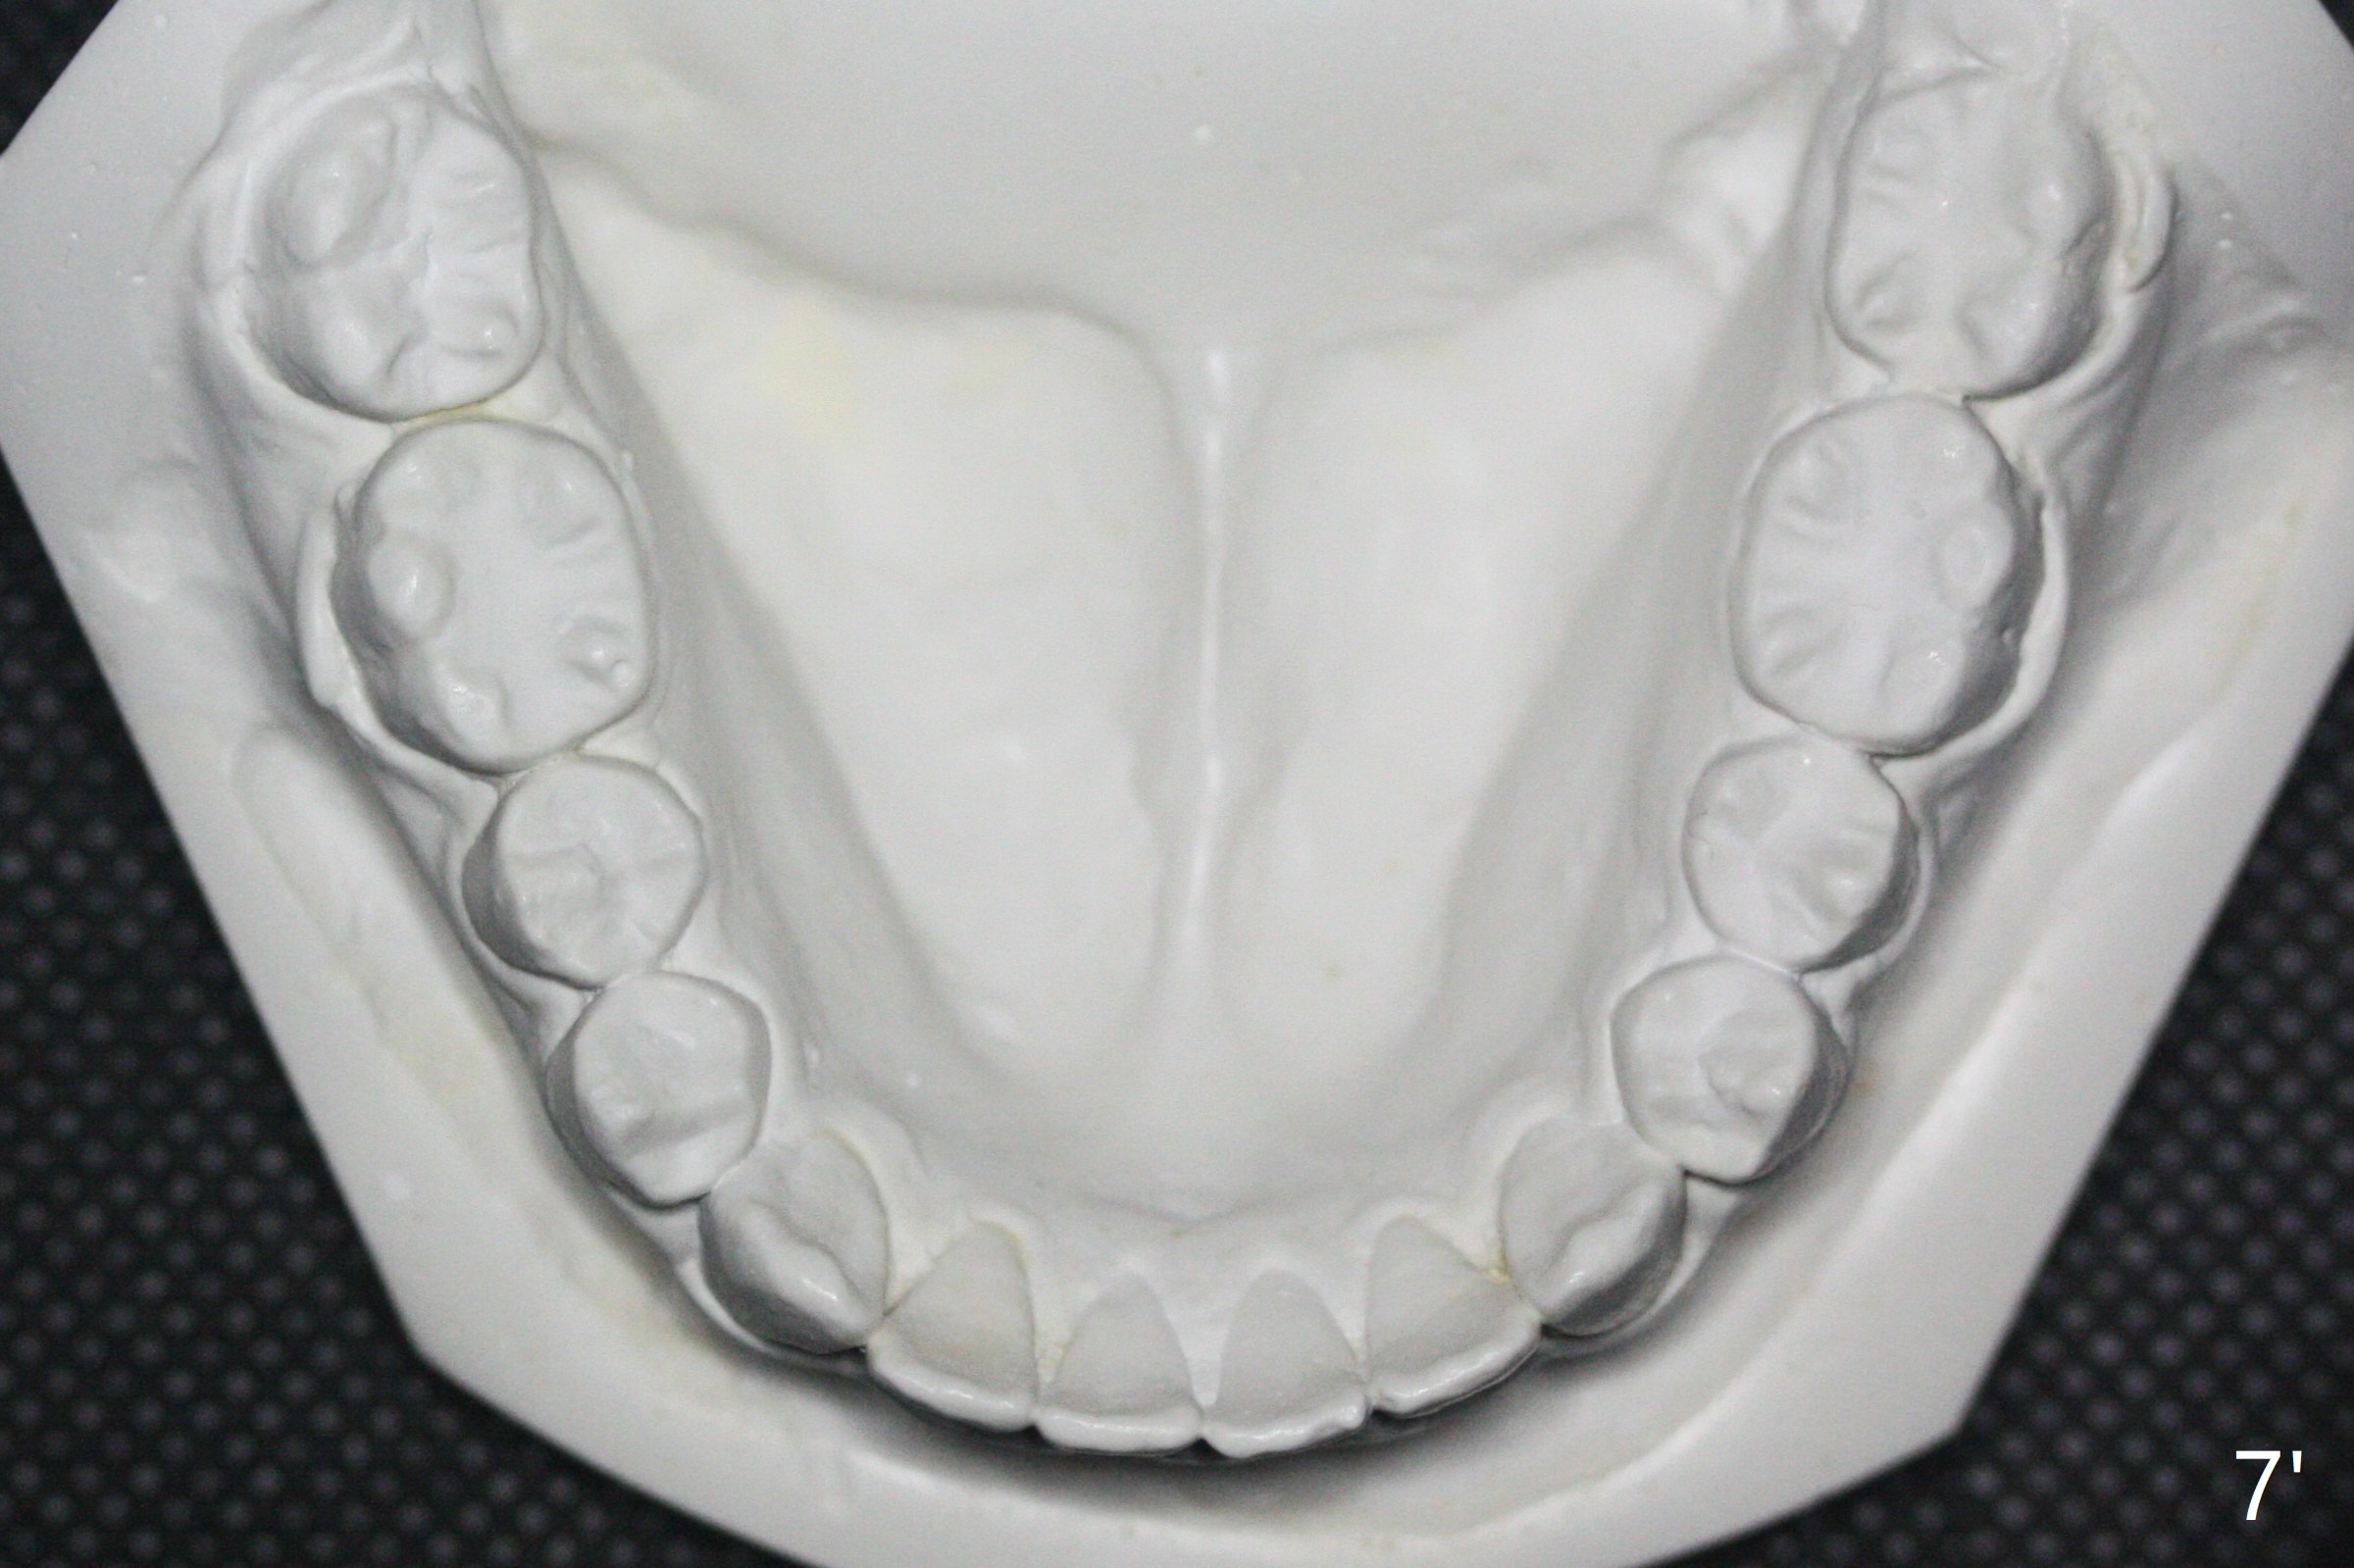

Bracketing for Congenital Missing Lateral